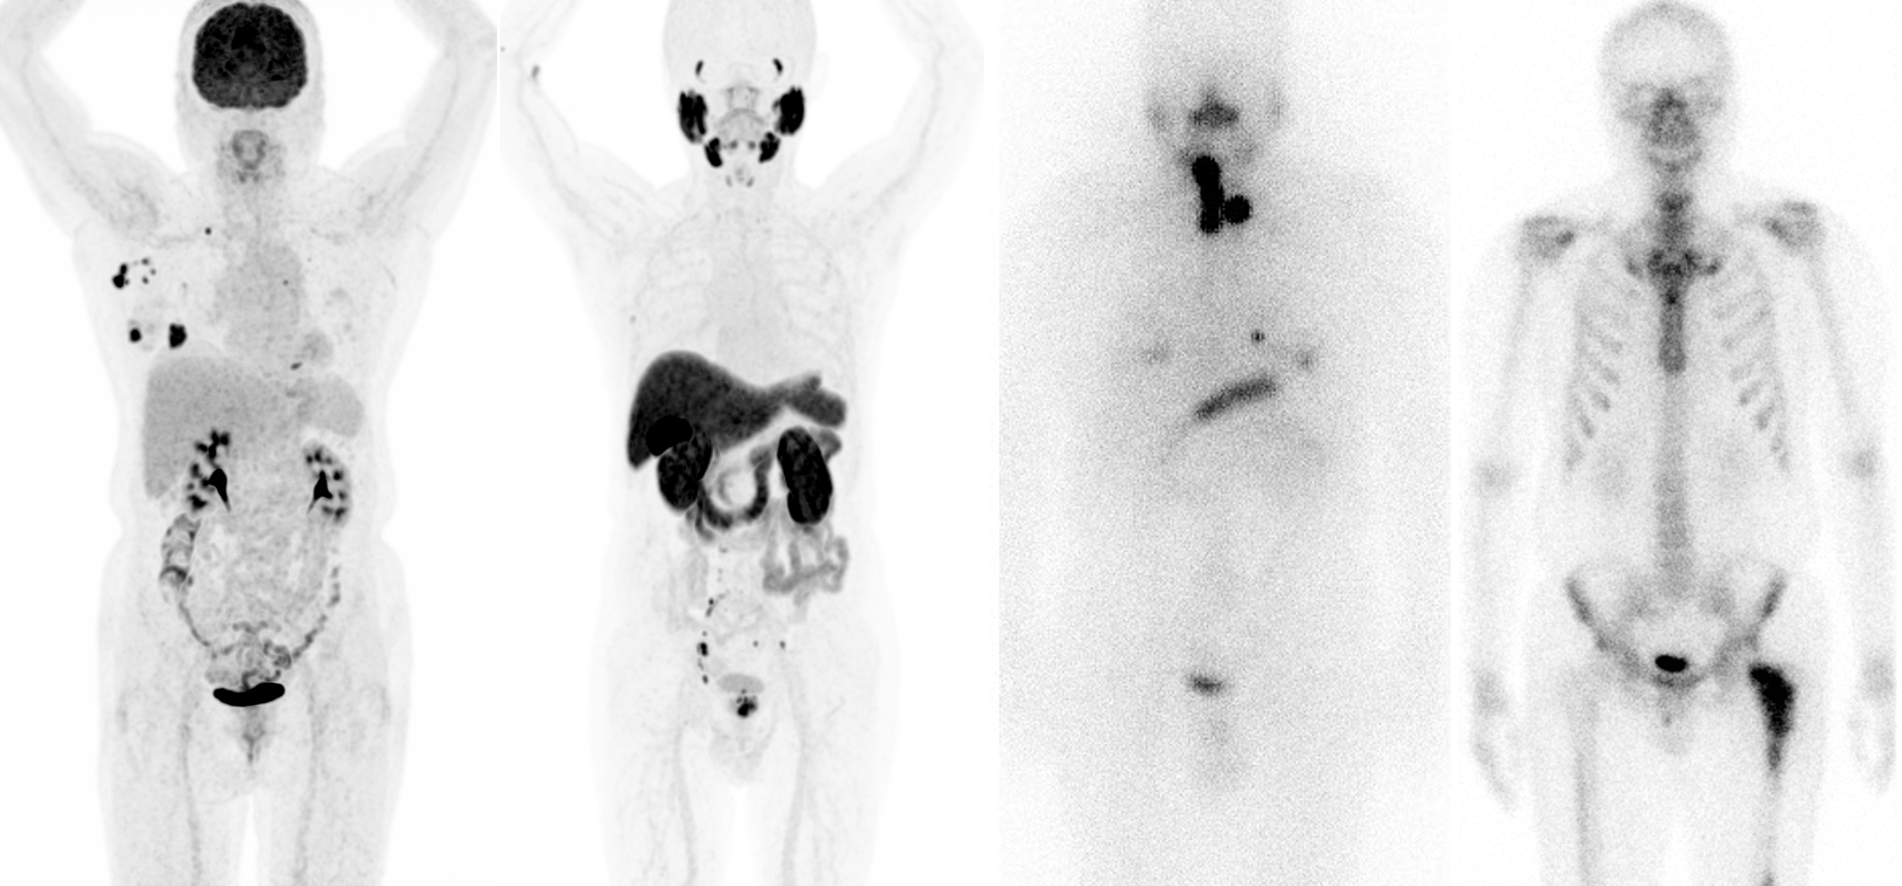

핵의학과는 방사성동위원소 및 방사성의약품을 이용하여 우리 몸의 상태와 질병을 진단하고 치료하는 의약의 한 분야로서 각종 암, 심장혈관질환, 뼈 질환, 비뇨기계 질환, 뇌혈관질환, 파킨슨병, 간질, 치매 등 다양한 퇴행성 뇌질환 환자들의 핵의학적 영상 진단을 담당하고 있다. 또한 동위원소 치료는 지속적으로 다양하게 발전하고 있으며, 갑상선암, 신경내분비 종양, 전립선암 등의 치료를 담당하고 있다.

진료 면에서 감마카메라, 단일광자단층촬영 (SPECT/CT), 양전자방출단층촬영(PET/CT)을 통한 감마영상과 PET 영상 건수는 지속적으로 상승하여 50여 종 가량의 다양한 영상 검사 및 핵의학 치료 들을 2024년 기준 한양대 서울병원 약 7천 건, 한양대구리병원 약 4천 건을 시행하고 있으며 명실상부한 한양대학교 의료원의 중심 진료과로 자리 잡고 있다.